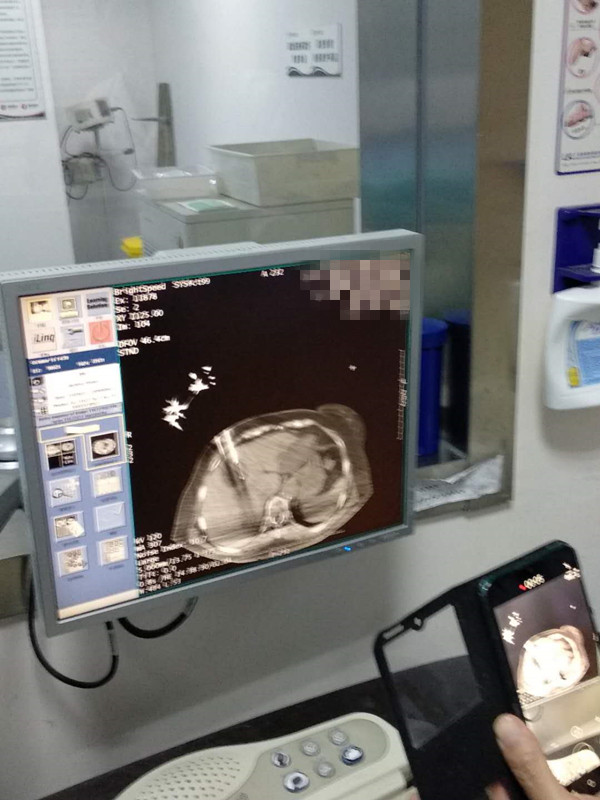

73岁患者肝部氩氦刀冷冻消融